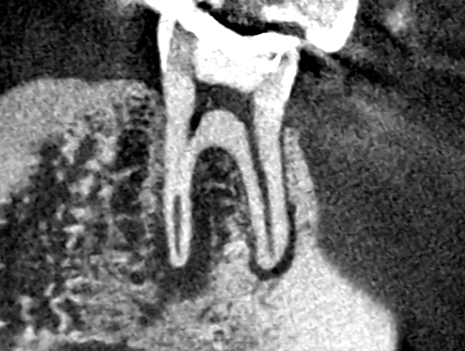

続きを読むVol.19 歯根破折を思わせるほど膿の影が大きくても、歯根破折しておらず根管治療で治ったケース

- 抜歯を避ける・ 歯を残す選択・ 歯根破折じゃなかった・ 精密根管治療・ 膿でも歯を残せる

抜歯をしたくないとのことで、当医院に来院された患者さんです。CT画像で確認したところ、上顎第一大…